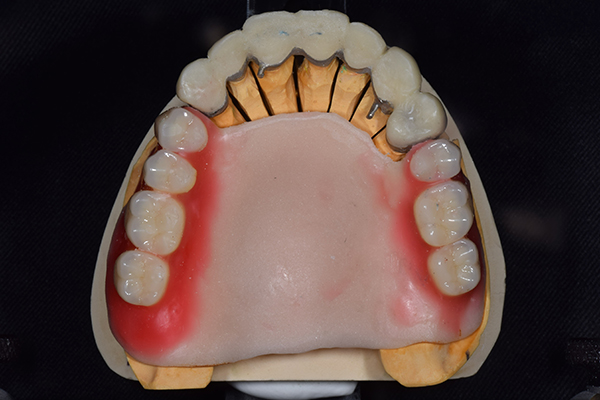

ケース2(自費の総入れ歯と部分入れ歯)

上下の入れ歯が外れやすくなったということでいらっしゃいました。 顎の骨はしっかりしていましたので、精密な型取りさえすればしっかりした入れ歯がつくれると思いました。 また下には6本歯が残っていましたが、虫歯になっている歯もありました。 かぶせ物のなかで大きな虫歯があった歯があり、1本だけ残せない状態でした。

上の入れ歯は確かに吸着は甘くなっていました。 また下の入れ歯はバネの一部が壊れており、安定感がなくなっていました。

精密な型取りの後、噛み合わせのチェックをしていきました。 かぶせ物も同時に作っていきました。

歯を並べた後、かぶせ物のフレーム作ってもらいました。先に歯を並べて理想の位置を決めておくことが大切です。

完成した入れ歯とかぶせ物です。 入れ歯への寛容度が高い患者様でしたので、 金属は使用せず、プラスチックのみで上は仕上げました。 下顎も歯は1本減ってしまいましたが、しっかり 入れ歯が維持できる様な構造にしました。

お口の中に入れた状態です。 見た目も最初とほとんど変わることなく作成できました。 維持や吸着に関しても問題ないようでした。

年齢 80歳・女性

主訴 上下の入れ歯が外れやすくなった

治療期間 3ヶ月

治療費 .メタルボンドクラウン:550,000円

.義歯:990,000円(税込、上下)

治療方針 長年使ってきた義歯の人工歯が磨耗し、臼歯部での咬合がすくなくなり、入れ歯の安定も悪くなり、あたりどころが悪くなって痛みが出ている。 そのため、入れ歯を上下作りかえる必要がある。

治療内容 過去に治療を行ったことのある歯が再度虫歯になってしまっているところがあり、すでに残せない状態にまでなっていたため、歯を一本抜歯した。 その後、かぶせ物と入れ歯を同時に作成していった。

特記事項 歯を抜いた後は、2〜3ヶ月歯ぐきの回復を待ってから入れ歯を作るため、待機期間があります。その間、古い入れ歯を調整しながらそのまま使うか、新し物をつくっておく必要があります。ただし、入れ歯は保険治療で作成する場合、6ヶ月は新しいものが作れないという決まりがあるので保険で全て作りたい場合は注意が必要です。